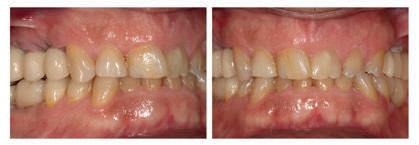

A PROPÓSITO DE UN CASO Paciente hombre de 52 años de edad que acude a la consulta demandando tratamiento implantológico para varias ausencias dentales y la restauración de los dientes remanentes (Figuras 1 y 2). El caso fue estudiado mediante modelos diagnósticos, exploración clínica y radiográfica.

Figura 1. Una imagen intra-oral mostrando la ausencia de piezas dentales en los sectores posteriores, la presencia de diferentes grados de desgastes dentales y raíces dentales remanentes.